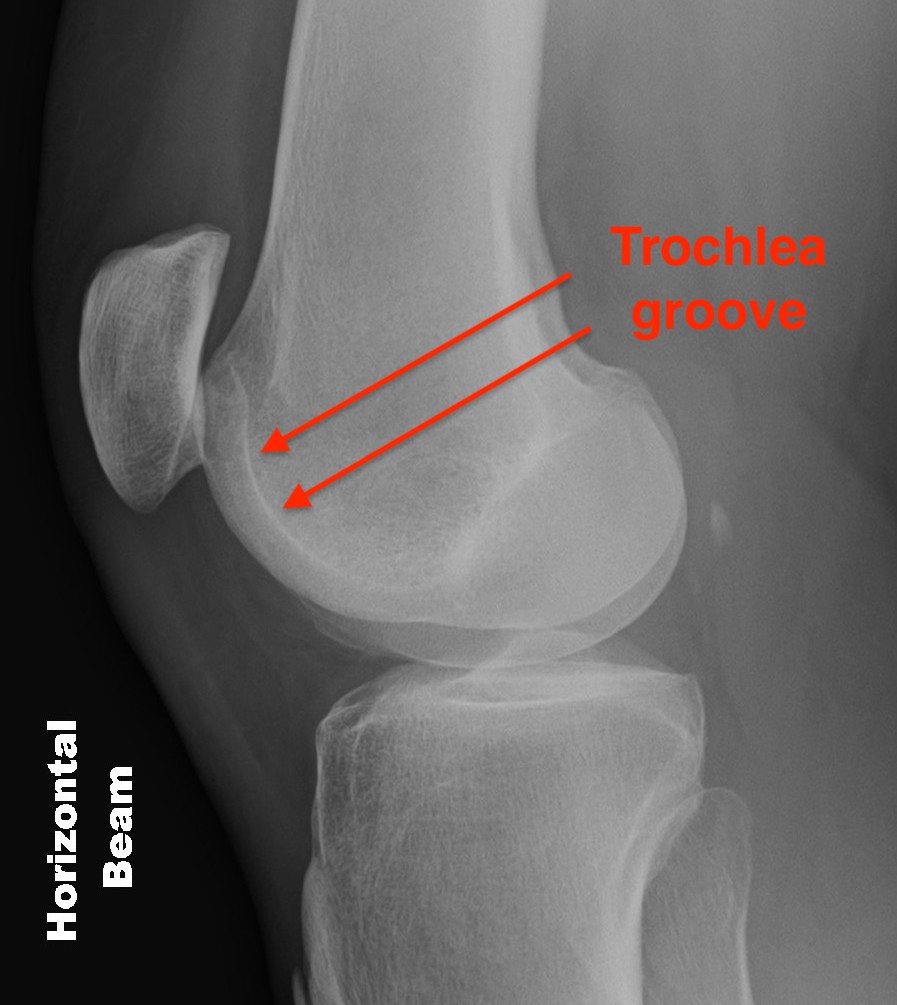

Trochlea Dysplasia / Dejour Crossover Sign

- lateral x-ray at 30o with condyles superimposed

- identify base of trochlea

- normal: clearly defined trochlea groove

- abnormal / Crossover: line of floor of trochlea crosses lateral lip of condyle

Normal trochlea / no crossover